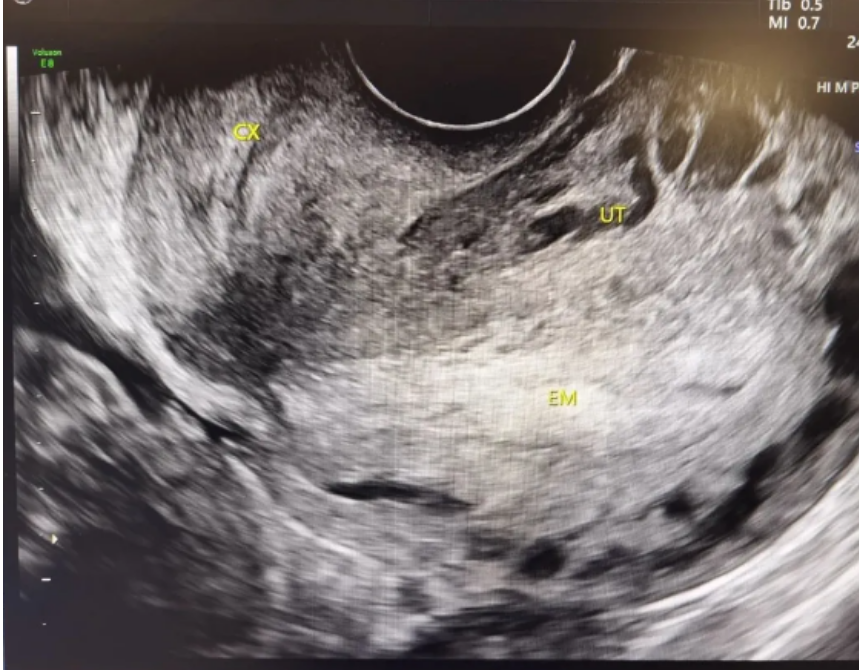

B超显示子宫切口憩室